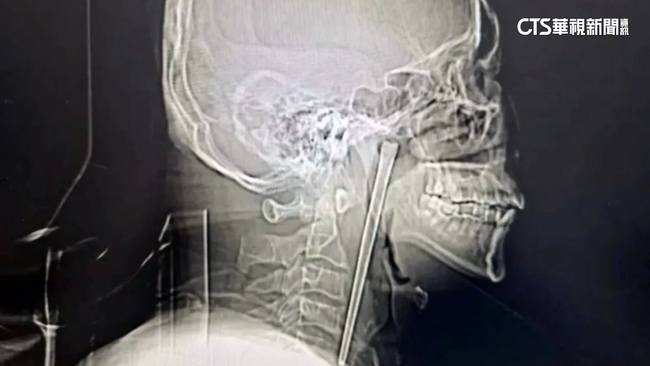

中國遼寧大連一名男子,8年前不慎把一根12公分的金屬筷子吞了下去,這根筷子就一直卡在他的咽喉部。

8年來,他雖然偶爾會出現輕微不適,但覺得還能忍受,又害怕動手術,就沒有去管他,直到最近感到明顯疼痛,才再次到醫院檢查。醫師表示,他的咽喉部黏膜沒有明顯破潰,聲帶活動也正常,甚至連喉腔也沒有受到壓迫位移,算是非常幸運。最後醫師為他進行微創手術,終於取出這根待在體內8年的長筷子。